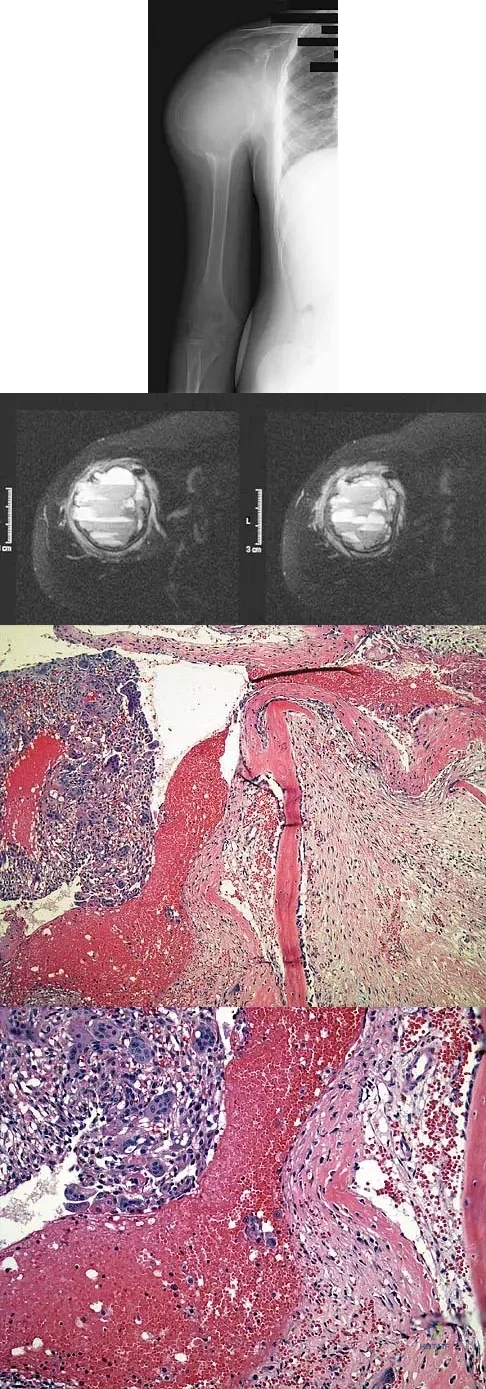

Question 92

A 15-year-old boy has had pain in the right shoulder for the past 3 months. He denies any history of trauma and has no constitutional symptoms. Examination reveals a large firm mass in the proximal arm. A radiograph and MRI scan are shown in Figures 27a and 27b. Biopsy specimens are shown in Figures 27c and 27d. Management should consist of

Explanation